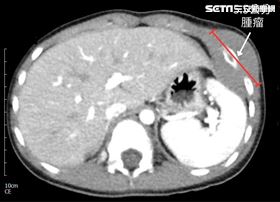

膽道雙癌纏身「免疫合併化療」力對抗病魔

一位45歲林小姐原本被診斷為乳癌肝轉移,經由肝臟切片...